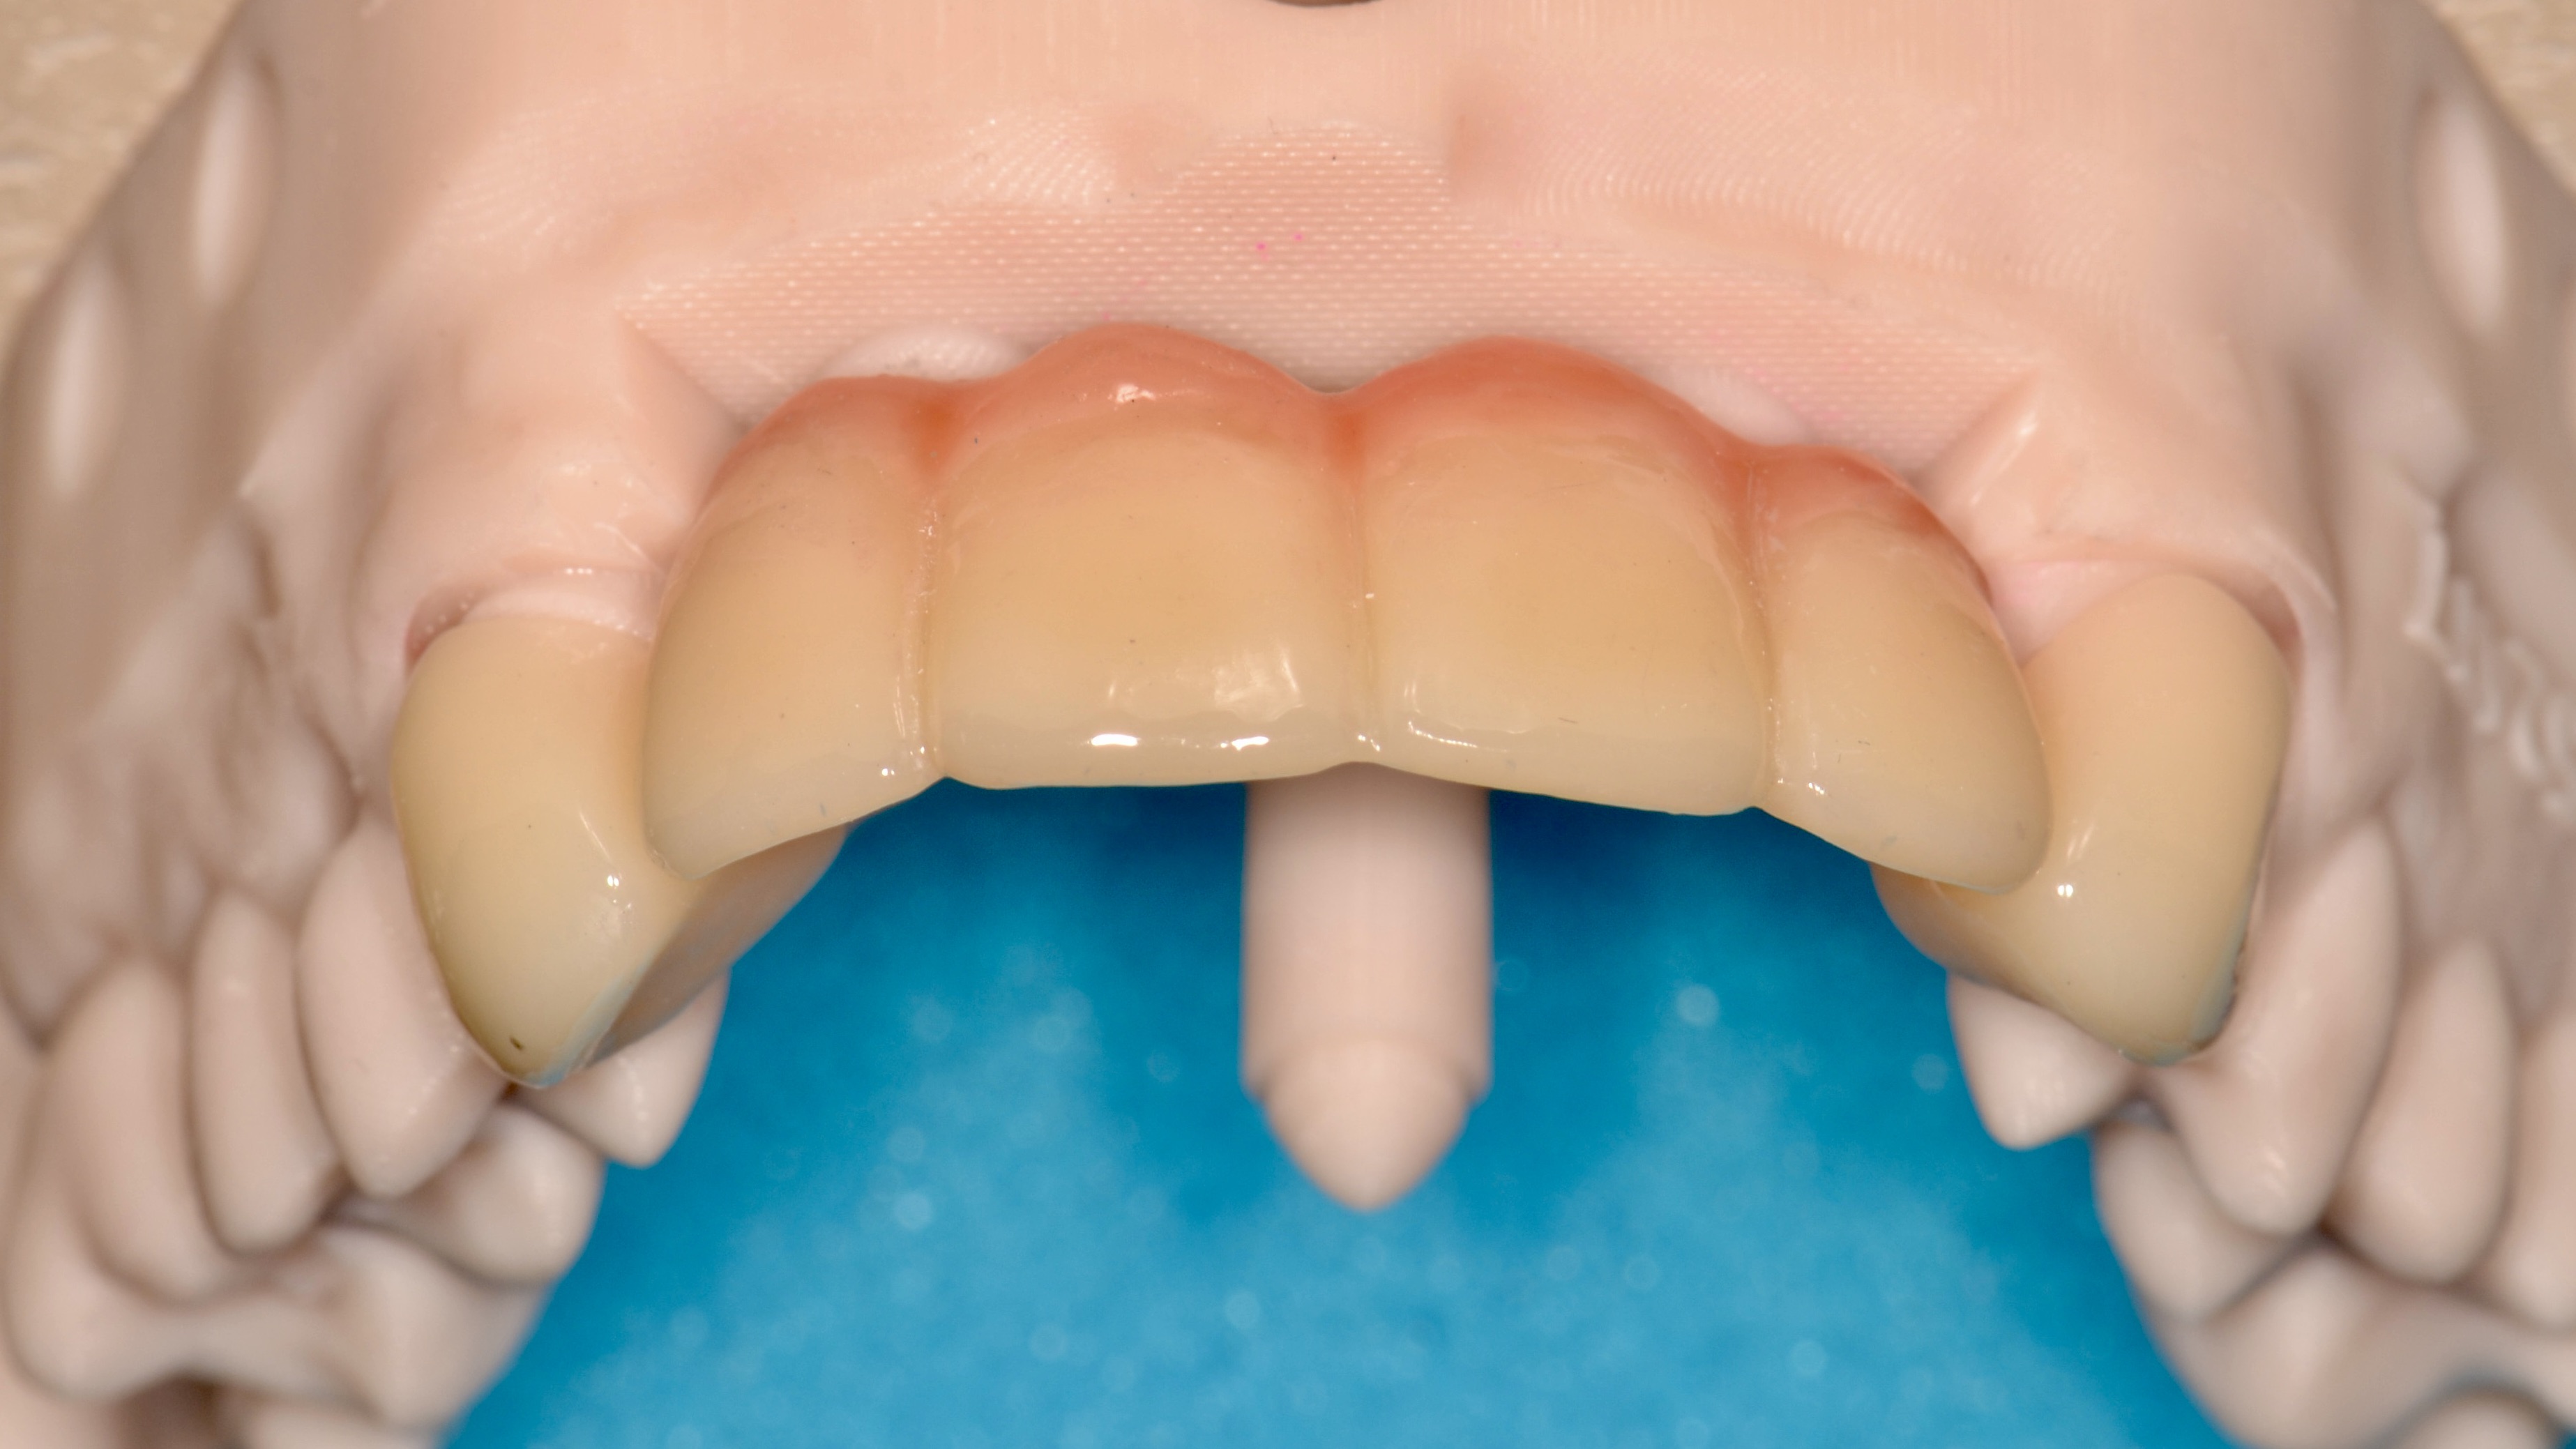

Ceramic Bridge